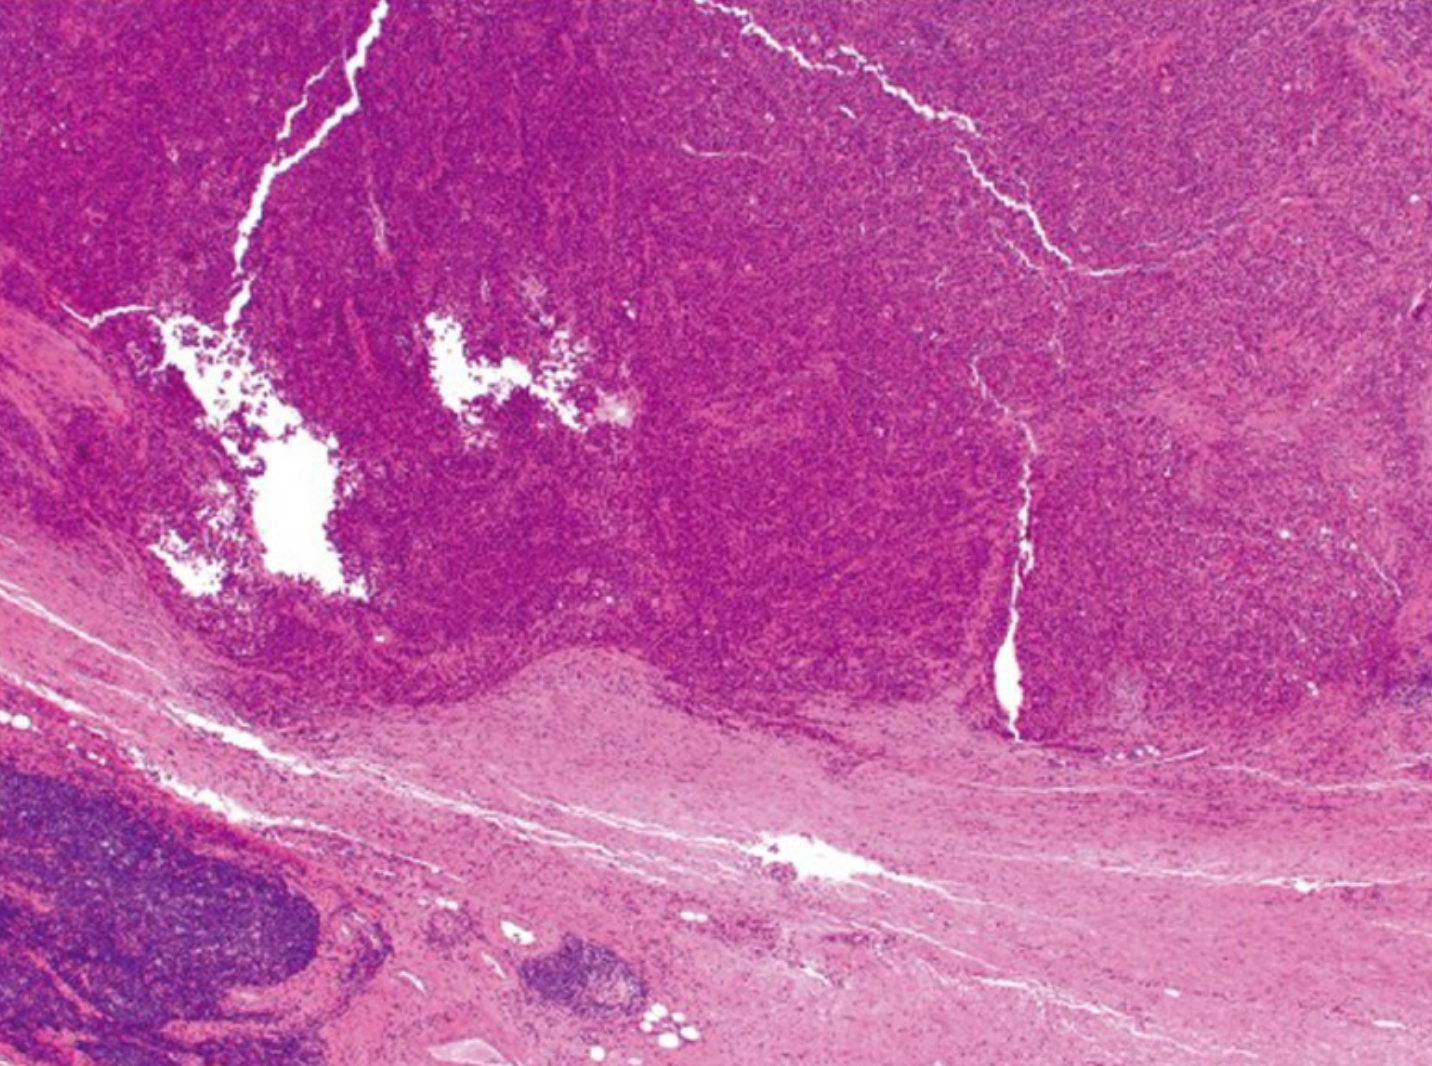

髓样癌极为罕见,每10000例结直肠癌确诊病例中约有5-8例。这种肿瘤的特征是上皮样肿瘤细胞片,具有大的泡状核,突出的核仁和丰富的细胞质。它通常在切除标本上有一个推动边界(图5),并且典型地与显著的肿瘤浸润淋巴细胞相关(图6)。髓样癌是一种独特的组织学亚型,尽管其组织学为低分化或未分化,但预后良好 [4]。

图5.髓样癌在肿瘤边缘呈推入性边界(原图×40)[4]。